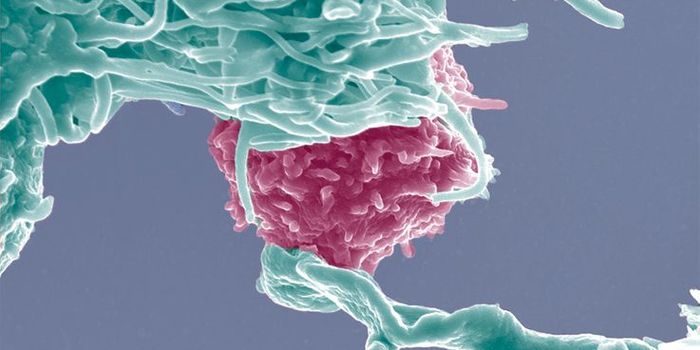

FEB 24, 2016Clinical & Molecular DXCancer cells are exquisitely cunning – they mutate and adapt to escape the body’s own defense mechanisms, an ...

MAR 19, 2015CancerResearchers at the Stanford University School of Medicine have discovered that when a certain aggressive leukemia is cau ...